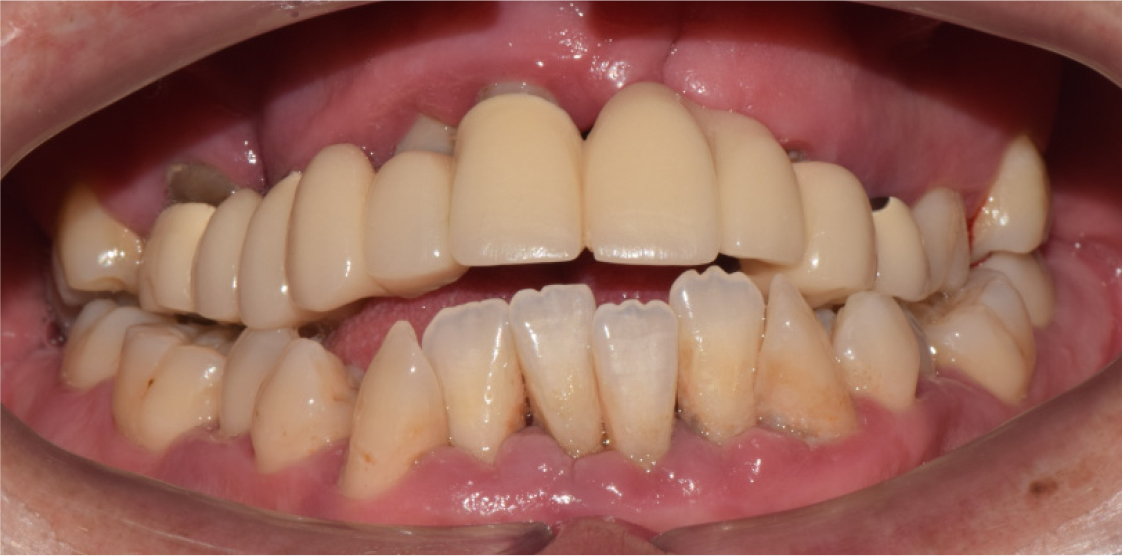

A 35-year-old man with left unilateral cleft lip and palate complained of pain in the maxillary right molar area. Approximately 25 years ago, the patient received treatment with a 10-unit fixed prosthesis with the maxillary right first molar, canine, and central and lateral incisors and maxillary left first and second premolars as the abutment teeth. The clinical and radiological examinations revealed residual roots of the maxillary right first molar and maxillary left first and second premolars due to severe caries. Moreover, severe alveolar bone loss was observed in the maxillary anterior area (Fig. 1). The maxillary right and left third molars were severely extruded because they had no opposing teeth. At maximum intercuspation, the bite was open, and there was occlusal interference between the molars on both sides due to eccentric movement of the jaw (Fig. 2).